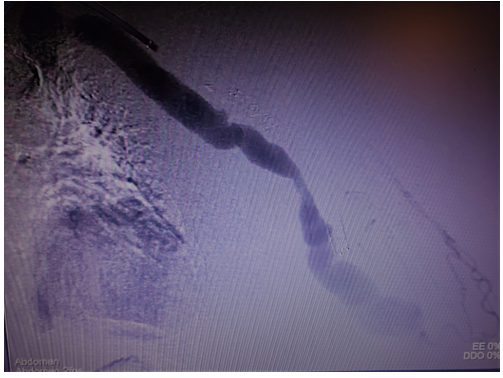

The Wrapsody stent was implanted through a basilic vein puncture, then a guidewire placement past the arterial stent femoral artery loop with a clothesline construction. Final arteriography demonstrated stent patency with excellent outflow. (Figures 5 and 6).

Figure 5: Postoperative image showing covered self-expandable Merit Wrapsody 8x125mm Merit Wrapsodyâ

Figure 6: Postoperative image showing Arteriovenous fistula patency.